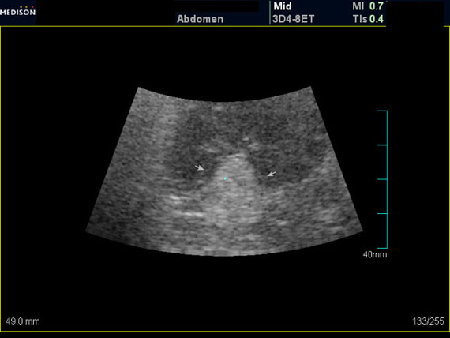

АНГИОМИОЛИПОМА ПОЧКИ

При ультрасонографии ангиомиолипома выглядит как округлое образование без капсулы с однородной внутренней эхоструктурой и четкими контурами; эхогенность ее чаще всего равна или чуть выше эхогенности перинефральной клетчатки [7]. Значительно реже эхогенность ангиомиолипом может быть равна эхогенности почечной паренхимы; такие опухоли состоят почти полностью из гладкомышечной ткани [8]. Иногда позади ангиомиолипомы может определяться слабая акустическая тень.

Большинство ангиомиолипом размерами менее 4 см протекают бессимптомно и требуют периодического наблюдения. Жалобы у больных обычно возникают при достижении опухолью размеров 4 см и более [9, 10]. Наиболее грозным осложнением таких образований является их разрыв с кровоизлиянием в периренальное пространство, что может сопровождаться шоком. На потенциально высокий риск разрыва ангиомиолипомы указывает наличие внутриопухолевой псевдоаневризмы, особенно размерами более 5 мм, — такие опухоли требуют превентивного хирургического удаления [11, 12]. При серошкальном ультразвуковом и доплеровском исследованиях псевдоаневризма выглядит как гипо- или анэхогенная структура с высокоскоростным «to-and-fro» («туда и обратно») кровотоком [13].